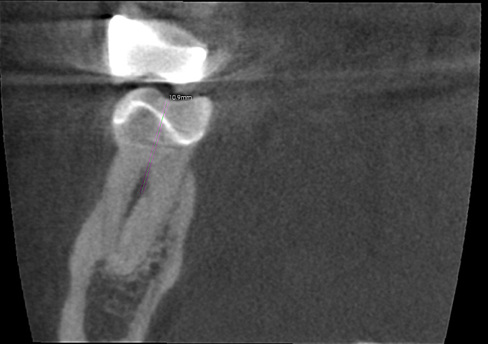

Instead of continuing to trough down the root with an ultrasonic tip or Munce bur, I opted to take an intra-operative CBCT scan with CAOH to provide an accurate road map of where the canals were located. Placing CAOH is helpful as the radio-opacity of the material can be used as a reference point. Additionally the CBCT scan has a ruler function indicates exactly how many millimeters further I need to navigate down the root. Using the scan prevents the unnecessary removal of radicular dentin and facilitates locating the canals.

I have included several different slices from the scan below:

Axial Slice in the apical third of the root suggesting the presence of separate portals of exit for each canal.

Distal Root, Coronal View, Arrow indicating the lingual split .